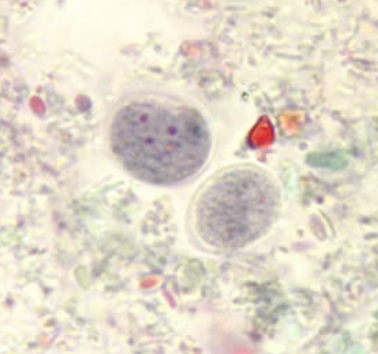

Endolimax nana (cyst)

Endolimax nana (cyst)